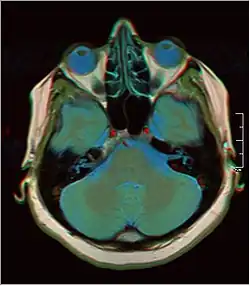

![]() Cross-sectional T1-weighted MRI of a healthy human brain acquired with an ultra high-field MR of 7 Tesla field strength | |

- T1-weighted (T1W) images: Cerebrospinal fluid is dark. T1-weighted images are useful for visualizing normal anatomy.